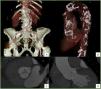

An 82-year-old woman with a history of hypertension and degenerative arthritis of multiple joints, ‘bamboo spine’, bilateral total knee and hip replacements (Figure 1) and blue-gray ocular deposits on both conjunctivae (Figure 1B), presented with New York Heart Association class III symptoms of heart failure lasting for six months. Transthoracic echocardiography revealed severe aortic stenosis (AS) with peak and mean aortic valve gradients of 105 and 61 mmHg, respectively, a valve area of 0.46 cm2, left ventricular hypertrophy and preserved systolic function. The coronary angiogram revealed non-significant stenosis in the left anterior descending coronary artery. Computed tomography angiography showed a porcelain aorta (Figure 2). Transcatheter aortic valve replacement (TAVR) with a 23-mm Edwards SAPIEN 3 valve was performed successfully.

Volume rendering technique (VRT) reconstruction of the abdominal aorta and iliofemoral arteries, the latter without significant calcification or stenosis (A); left anterior oblique VRT reconstruction of the thoracic aorta, disclosing extensive, multifocal calcified plaques (porcelain aorta) (B); short-axis (C) and coronal (D) reconstructions of the aortic valve at 20% of the RR interval, disclosing restricted systolic leaflet motion and mild commissural calcification.